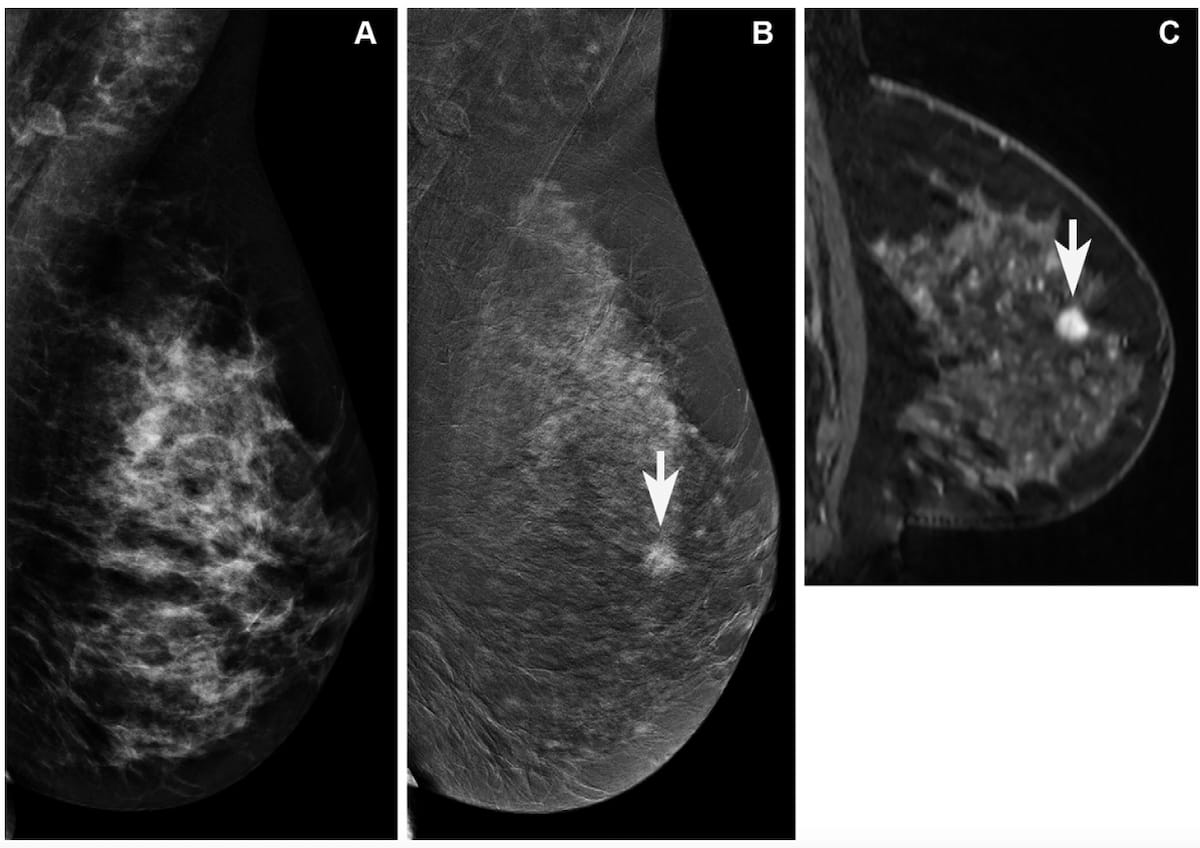

In a new study comparing standard breast MRI, abbreviated breast MRI and contrast-enhanced mammography in supplemental breast cancer screening, researchers found that MRI offered a greater than 14 percent higher cancer detection rate and a nearly 39 percent higher sensitivity rate than CEM.